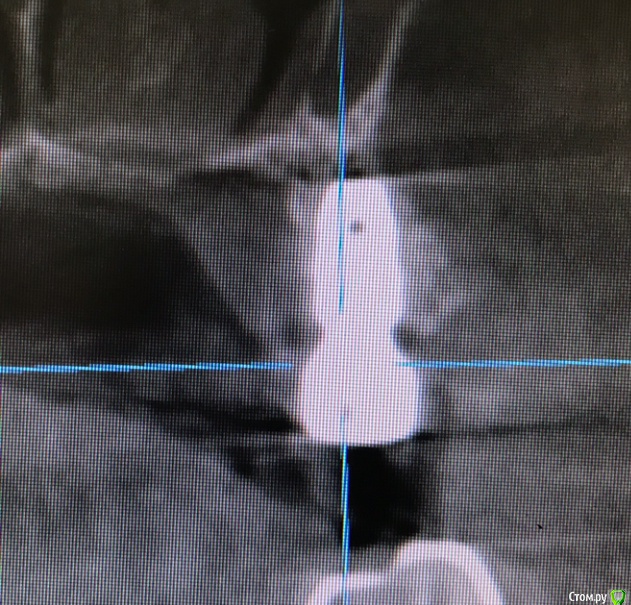

колесников Опубликовано 20 августа, 2019 Автор Поделиться Опубликовано 20 августа, 2019 Очередной случай тоннельной пластики альвеолярного гребня. Был небольшой бонус в виде лунки 26го зуба с дефектом вестибулярной стенки и оас. Лунка консервирована и закрыта «быстрым Ноймайером»,24,25 тоннельный графтинг. Графт тот же,шурос кортикальный без добавок.Контроль и имплантация через 4 мес,через неделю фиксация временной реставрации. Через 2-3 проверим на состоятельность. 4 Ссылка на комментарий